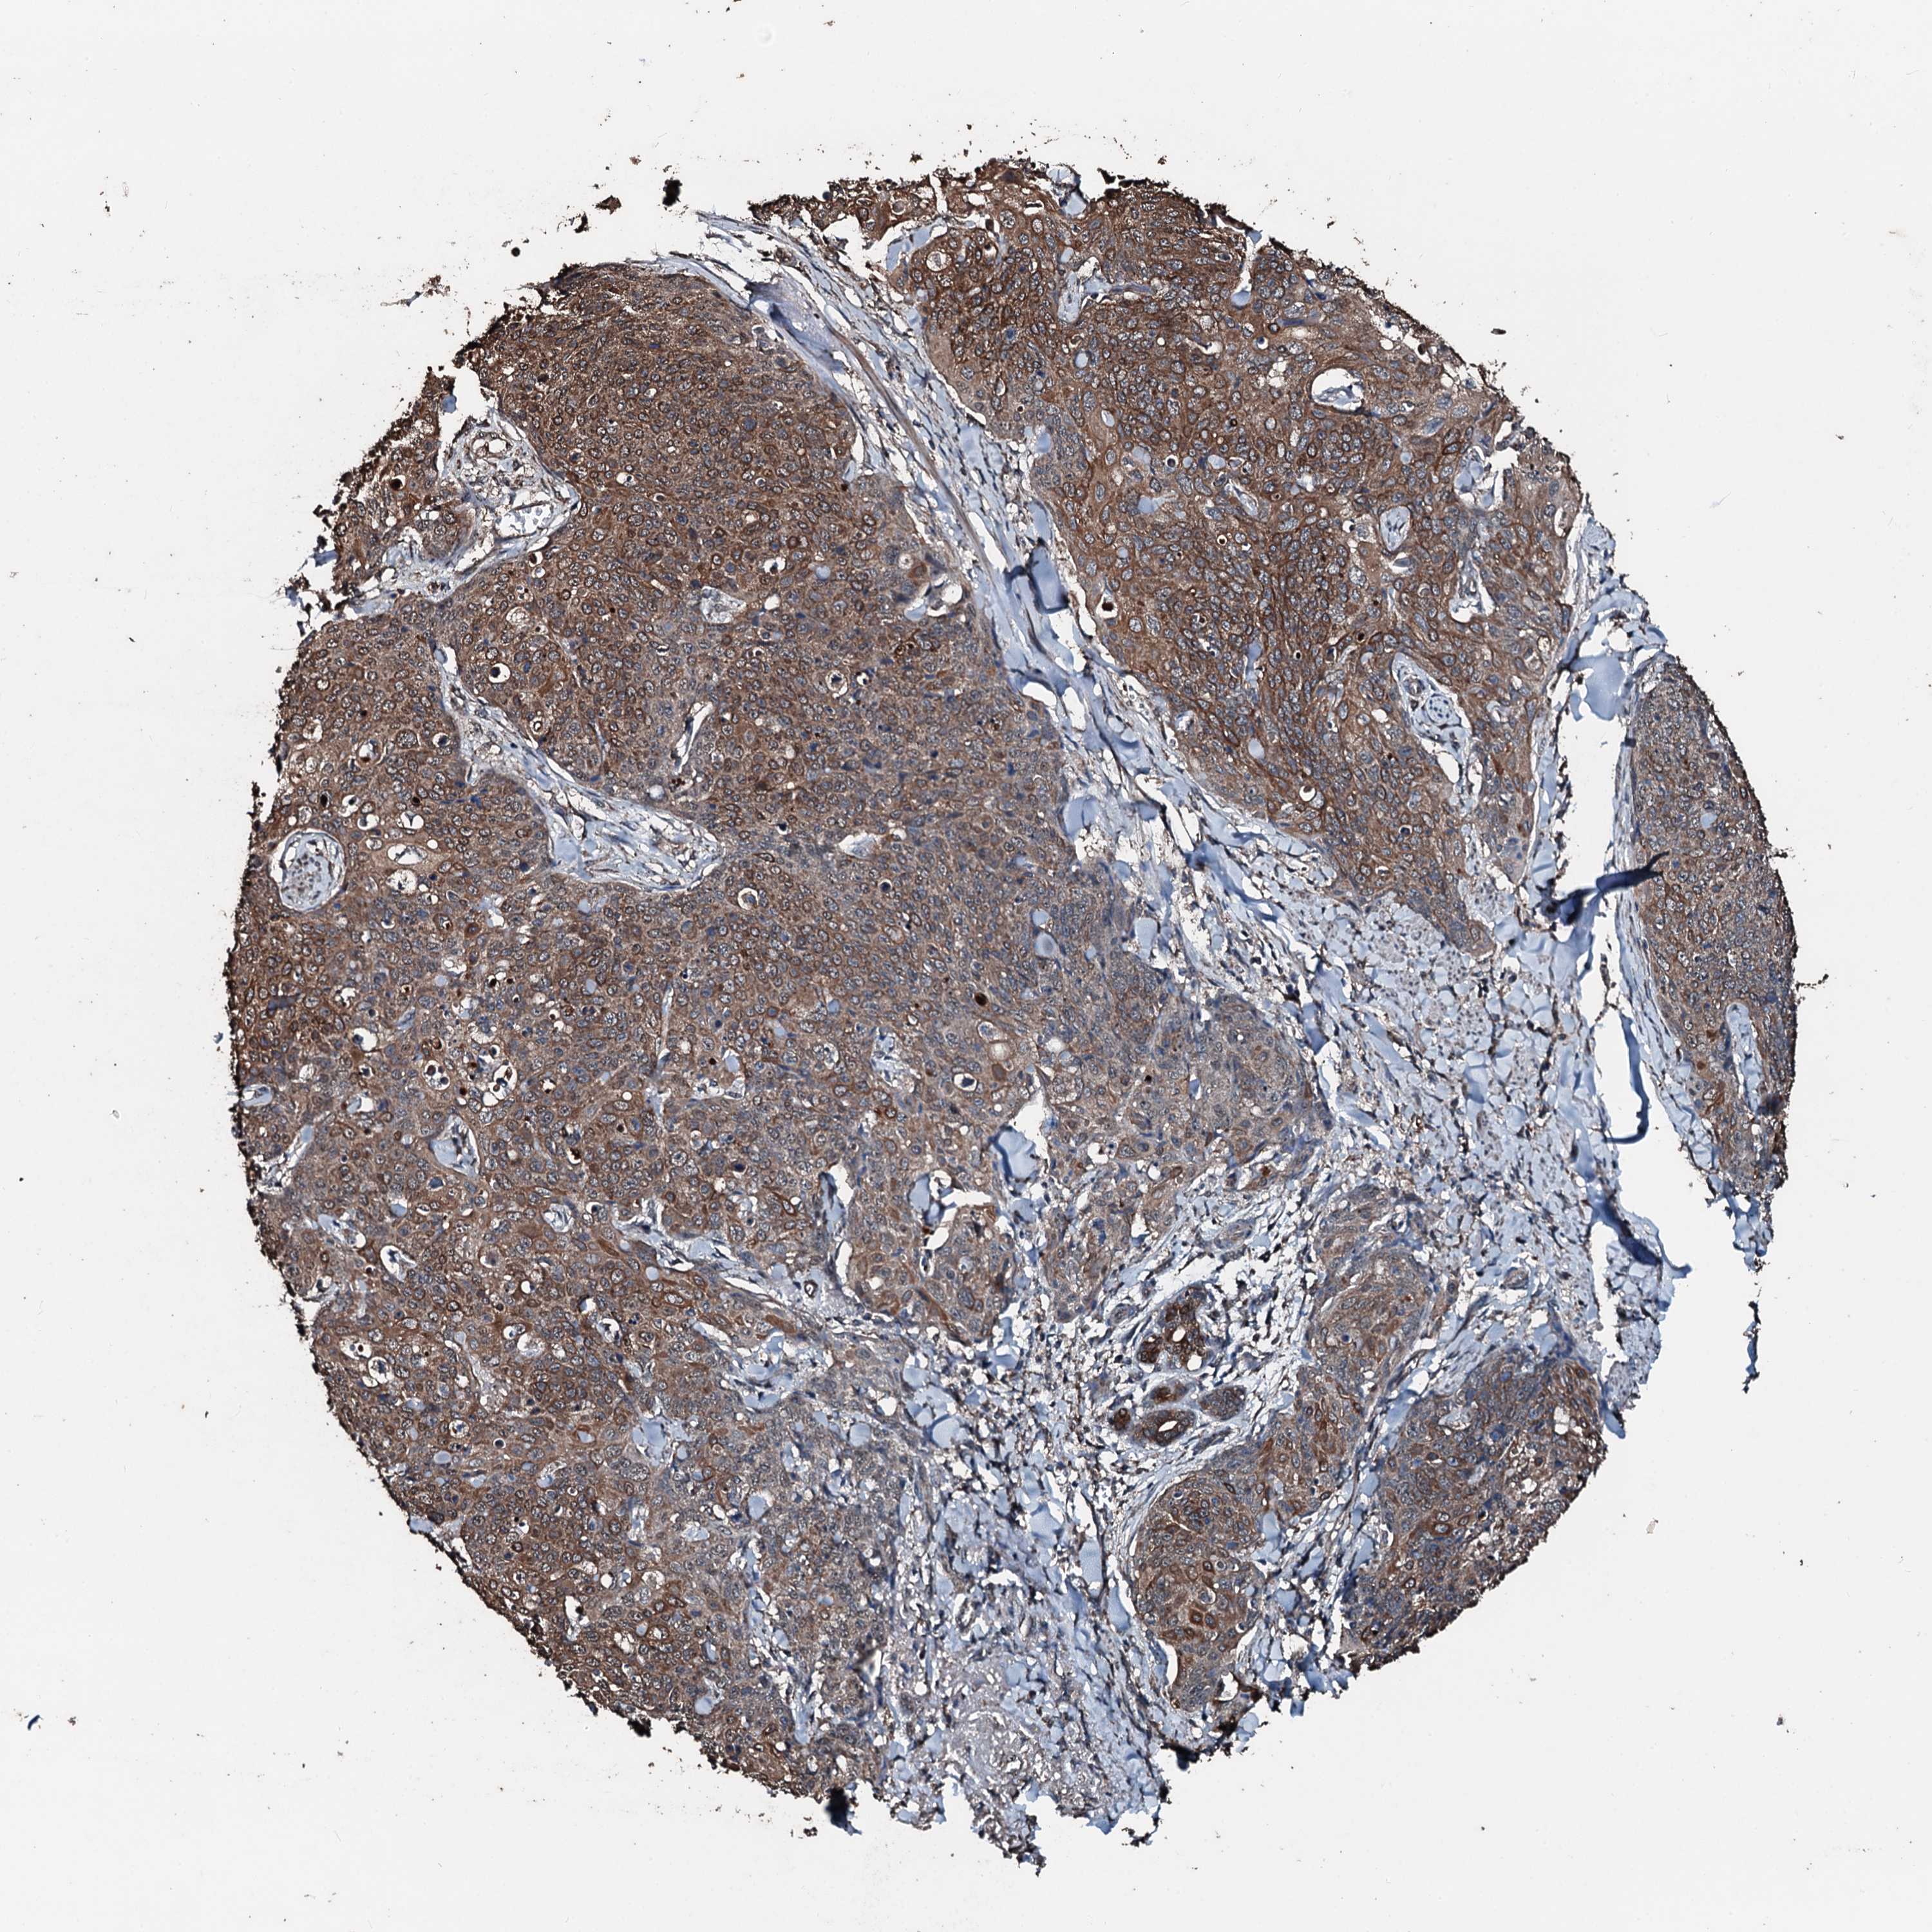

SKIN CANCER - Protein expressioni

A mouse-over function shows sample information and annotation data. Click on an image to view it in a full screen mode. Samples can be filtered based on level of antibody staining by selecting one or several of the following categories: high, medium, low and not detected. The assay and annotation is described here.

Antibody staining in the annotated cell types in the current human tissue is reported as not detected, low, medium, or high, based on conventional immunohistochemistry profiling in selected tissues. This score is based on the combination of the staining intensity and fraction of stained cells.

Each image is clickable and will lead to virtual microscopy that enables deeper exploration of all samples and also displays staining intensity scores, fraction scores and subcellular localization as well as patient and tissue information for each sample.

Antibody HPA041168

Squamous cell carcinoma, NOS

Squamous cell carcinoma, metastatic, NOS